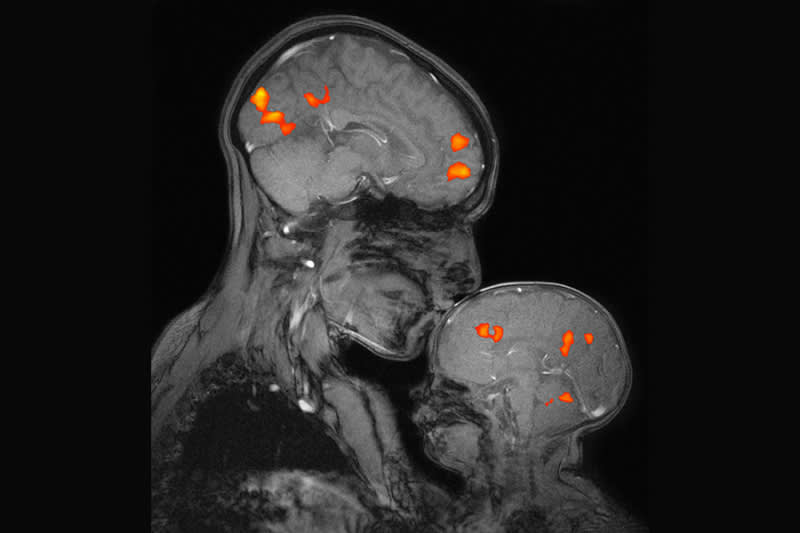

For 25 years, the McGovern Institute at MIT has led groundbreaking research in neuroscience, neurotechnology, AI, and therapeutics, driven by a vision to understand the human brain and improve lives globally. Notable achievements include the development of the CRISPR gene therapy, prosthetic limbs controlled by the nervous